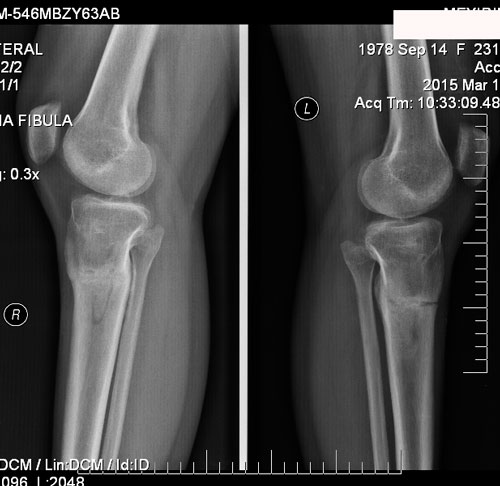

Это мои ножки. Сегодня 5 день. До сих пор не верю, что это происходит со мной. Как будто это сон. У меня двое маленьких детей, быт, куча дел, все не решалась, все думала как я их оставлю, как они без меня. Но все таки решилась! Ура! Я рада, что приближаюсь к своей мечте! Терпения, конечно, надо немалого, но мысль о ровных красивых ножках дает столько сил. Нас в данный момент двое, я и loginza499, у нее сегодня 18 день, исходники наши почти похожи, только ножки у нее худее. У нее уже заканчиваются Крутки и я вижу ее результат, ножки реально стали ровными. Я рада за нее и ее результат мне придает столько сил и уверенности. А в общем что касается больницы, персонала, то мне все нравится. Все вежливые, спокойные. Тут бессменная, незаменимая Маришка, молодец! Во всем поможет, позаботится. Кто лежал, знают.